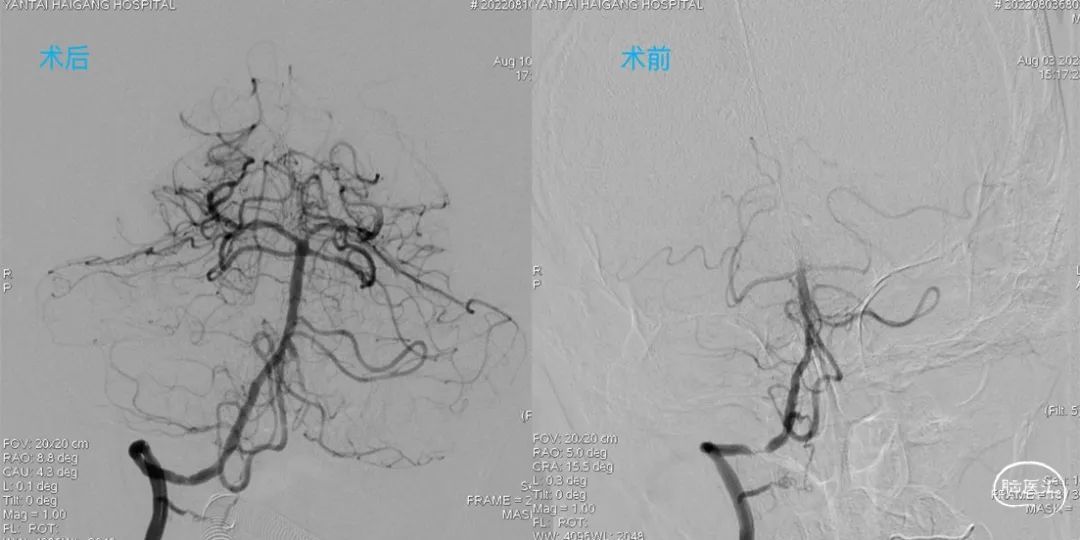

术后影像

术后即刻影像及患者术后情况:

造影见狭窄位置狭窄解除,支架贴壁良好,后循环各分支动脉显影良好。术后次日患者行走不稳情况明显改善,术后1月随访患者行走如常,未再发头晕。